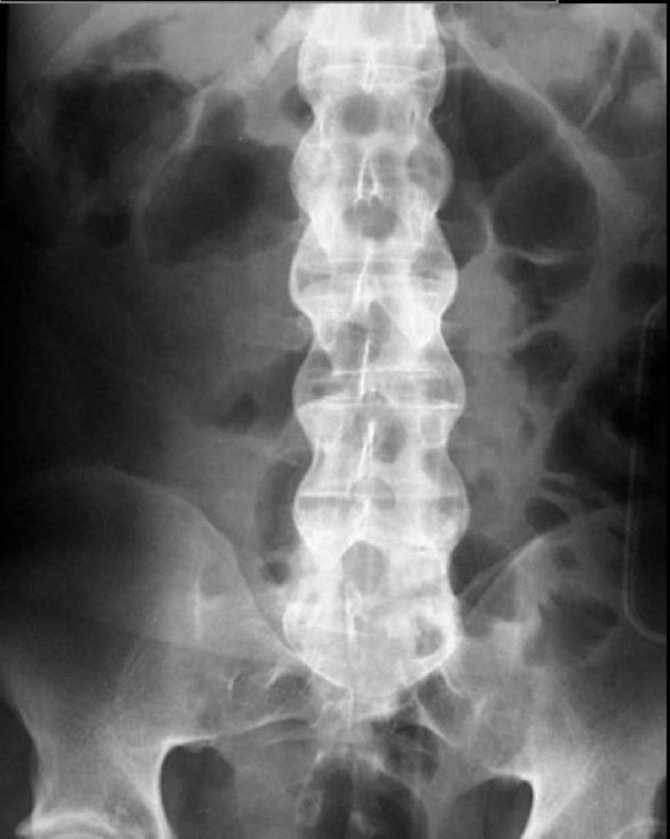

Gece ağrıları içinde en önemli olanların kanser ağrıları olduğunu fakat bu ağrıların nadir olup ileri yaşlarda rastlandığını aktaran Bahadır, “Daha sık rastladığımız gece ağrısı genellikle genç ve orta yaşlarda görülen, sabaha doğru artan ağrılardır. Eğer bu ağrıya birde sabah tutukluğu ekleniyorsa iltihaplı omurga romatizması yani bilinen adıyla ankilozan spondilit hastalığı olma şansı çok yüksek demektir. Ankilozan Spondilit genelde omurgayı bazen omurgaya ek olarak kalça ve diz gibi büyük eklemleri tutan sakatlayıcı bir hastalıktır. Yıllar içinde tüm omurga kemiklerini birbirine yapıştırıp hastayı öne doğru iki büklüm eğer. En önemli özelliği genelde çok sinsi ilerlemesidir. Ağrı ve hareket kısıtlılığı çok yavaş ilerlediğinden kişiler bunu pek önemsemez. Bu sinsi ilerleme yüzünden ilk ağrı şikayetlerinin başlamasından sonra ortalama tanı konma süresi dört beş yılı bulmaktadır. Bu nedenle Ankilozan Spondilit hastalığının en önemli ve erken bulgusu olan gece omurga ağrısı olanlar, hele hele bu ağrıyla beraber sabah tutukluğu şikayeti de olan hastalar çok geç olmadan doktora başvurmalıdır. Yalnız burada bahsettiğimiz sabah tutukluğu herkeste olabilen birkaç dakikalık sabah hamlığı değildir. En az 30 dakika (bazen bir iki saat olabilir) omurga hareketlerini istense de tam yapılamaması ve omurgasının etrafında aşırı bir sertlik hissedilmesi halidir. Genelde birkaç saat içinde bazen öğlene doğru bu sertlik gider ve hasta normal hareket etmeye başlar. Ertesi sabah aynı senaryo tekrarlanır. Bu nedenle bel-sırt bölgesinde sabah tutukluğu uzun süren kişiler en kısa zamanda doktora başvurmalıdır” diye konuştu.

Ankilozan spondilit hastalığının tedavisinde tıbbın artık 15 yıl öncesinde olduğu gibi çaresiz olmadığına dikkat çeken Bahadır, “Yeni çıkan biyolojik tedaviler ile son 10 yılda hastalığın tedavisinde büyük ilerlemeler kaydedildi. Bu hastaların en büyük sorunu olan ve omurga hareketine izin vermeyen dirençli ağrılar artık bu ilaçlar ile kontrol altına alınabilmektedir. Ankilozan spondilitte omurga hareketlerinin kısıtlanmasını önleyen en önemli tedavi ilaç değil egzersizdir. İlaçlar ile ağrı düzeltildikten sonra hastaların düzenli egzersiz yapması ile omurganın eğilmesi engellenebilmektedir. Ama asıl problem hastalığın tanısını erken koymaktır ve omurga kemikleştikten sonra ne ilaç ne egzersiz bunu düzeltemez. Bu nedenle geceleri bel-sırt ağrıları ve sabah tutukluğuna dikkat diyoruz” şeklinde konuştu.